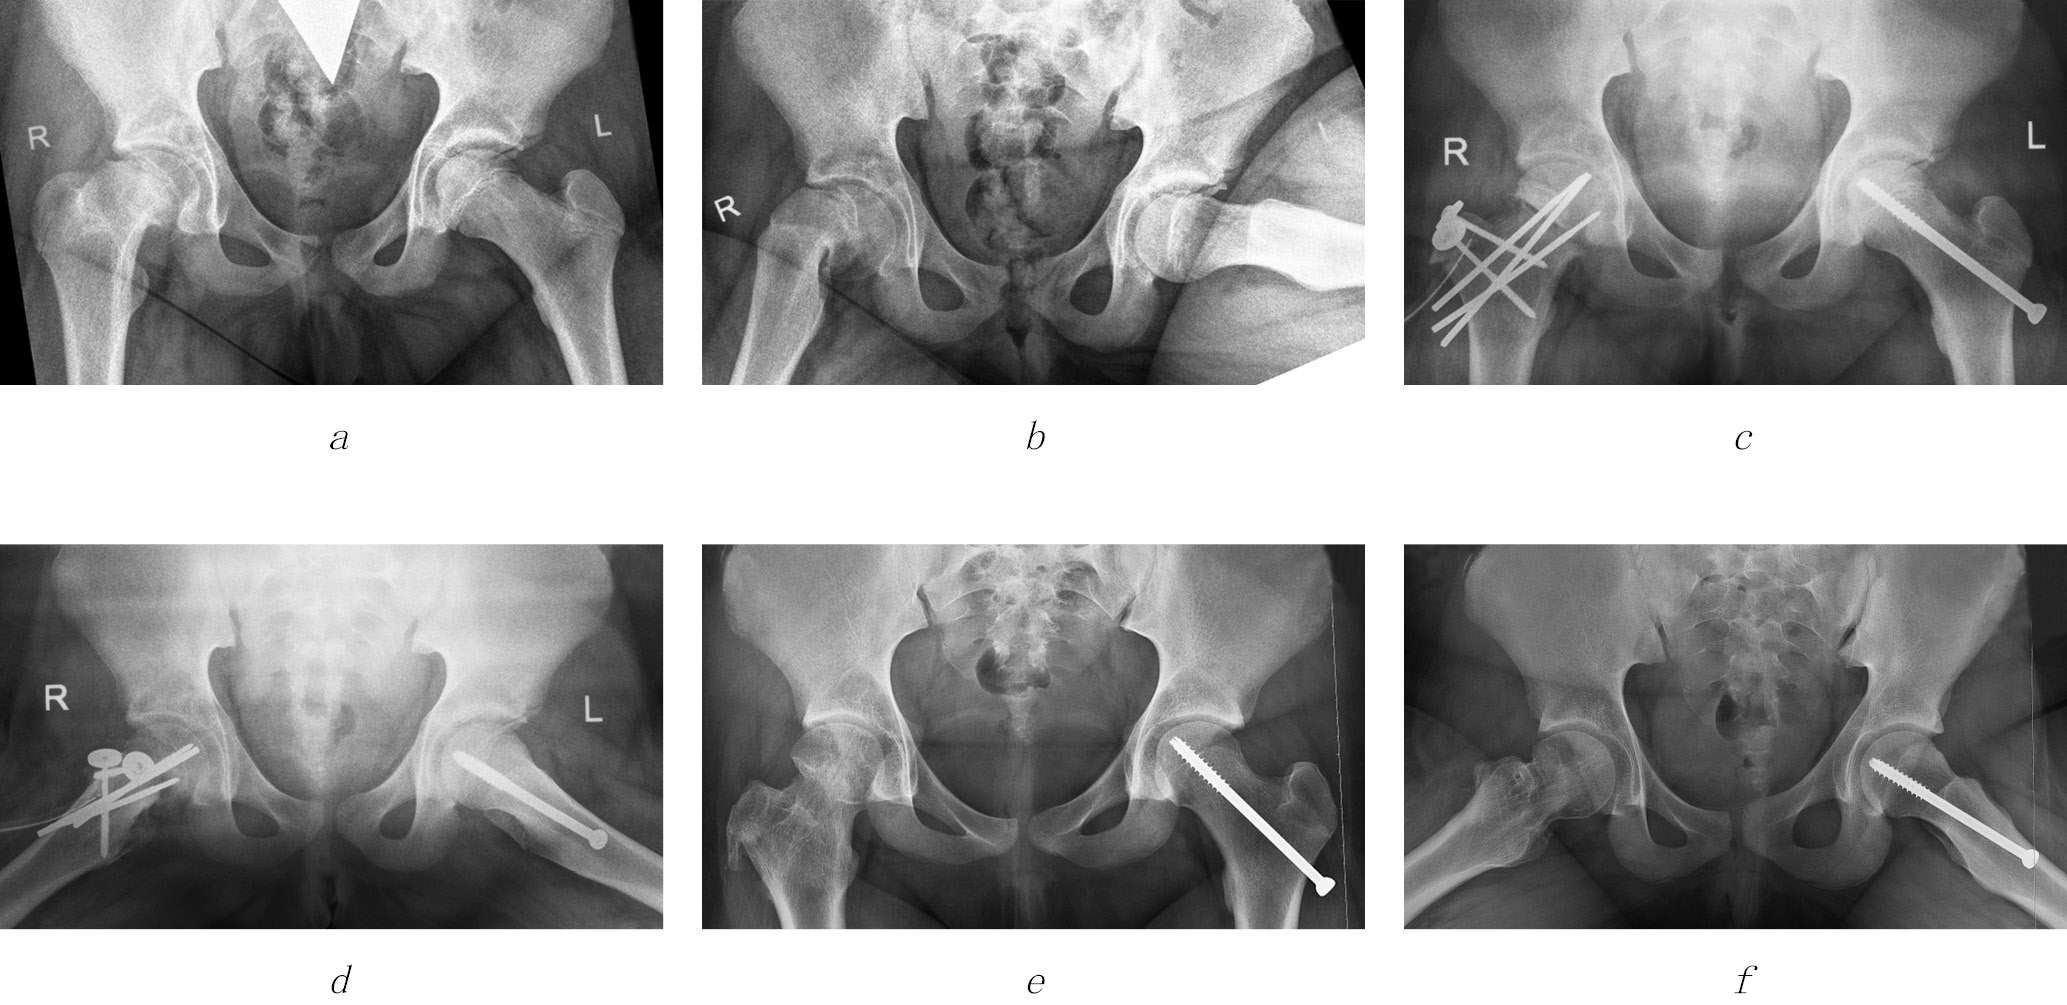

An X-ray examination of the hip joints in standard projections (anteroposterior and by Lauenstein) in the preoperative period was performed to assess the direction and degree of epiphysis displacement, the nature and severity of the metaphysis deformity, and the severity of the pathological process in the contralateral joint, as well as to avoid early complications of SCFE. In the presence of an acute displacement in the history, the degree of synostosis of the epiphysis and metaphysis was determined. The degree of posterior epiphysis displacement was estimated by the difference between the values of the epiphyseal angle in the joint without displacement and in the affected joint, and the degree of downward displacement was determined by the difference between the projection caput-collum-diaphyseal angle and epiphyseal-diaphyseal angle in the affected joint. Out of nine cases with a chronic epiphysis displacement and an acute displacement with the chronic one, in five cases, a posterior-downward displacement was revealed, and in four cases, there was only a posterior displacement, with a posterior displacement of 63−86°, and a downward displacement of 7−19°. In one case with a primary-acute epiphysis displacement, the latter occurred only downward and amounted to 32°. Severe deformity of the femoral neck was registered in 9 out of 10 patients, the neck was bent downward and posteriorly (a swan neck symptom) in accordance with the direction of the chronic epiphysis displacement, and in only one patient with primary-acute displacement, it had a normal shape. In joints with an acute epiphysis displacement, the transition of the anterior surface of the femoral neck to the head was always step-like, and in joints with chronic displacement, it was smooth. In all 10 affected joints in the femoral neck, directly under the epiphyseal growth plate, the foci of osteoporosis were traced, located separately and merging with each other and with the growth plate. In three cases, similar changes were also found in the contralateral joint. In all five joints with acute displacement and in three joints with chronic displacement, diffuse osteoporosis of the epiphysis was noted. It should be emphasized that none of the 10 affected joints had signs of aseptic necrosis of the femoral head or chondrolysis. A sign of synostosis of the epiphysis and metaphysis, which began after an acute displacement, was the presence of newly formed bone tissue with a trabecular structure between them. The degree of synostosis depended on the number of these sites (the so-called bone bridges), the number of which was determined by a CT scan if necessary.

Radiography of the hip joints in standard projections was also performed on the operating table immediately after completion of the intervention. These radiographs mainly evaluated the spatial position of the epiphysis after correction and the correct location of the hardware installed. The minimum residual displacement (within 5°) was maintained in 6 out of 10 affected joints (posterior to downward in 2 cases, only posterior in 3 cases, and only downward in 1 case). Hypercorrection of the epiphysis position was not allowed in any case.

On radiographs a month after the surgery, in all 10 cases, stable fixation of the epiphysis and greater trochanter was noted without loss of correction of their position and initial signs of consolidation at the level of osteotomies. In six of the eight joints with diffuse osteoporosis of the epiphysis, its severity increased slightly, and osteoporosis of the epiphysis appeared in two more joints. In a clinical study, none of the patients had a vicious position of the limb, but its relative shortening persisted; in four cases, the latter increased by 0.5–1.0 cm. In all patients, the amplitude of the hip movements increased significantly, with soreness at the extreme points. The Drehmann symptom in all joints was negative.

Upon X-ray examination of the first seven patients, 6 months after the surgery, in all cases, the spatial position of the epiphysis and the greater trochanter had not changed, and there were signs of completion of consolidation at the osteotomy level. In two cases, the initial phenomena of aseptic necrosis of the femoral head were noted, but in five others, there was a significant decrease in the severity of the epiphysis osteoporosis. There were no signs of hip chondrolysis in any cases. Clinically, in five joints with positive X-ray changes, an even greater increase in the amplitude of hip movements was revealed, and in one of the joints with incipient epiphysis necrosis, there was a slight decrease associated with the development of secondary synovitis. In all seven patients, at month 7 of the postoperative period, the hardware was removed.

One year after surgery, a clinical and radiological examination was performed on the first five patients. Radiographic signs of aseptic necrosis of the femoral head were found only in one of them, in the joint, in which epiphysis necrosis had already begun, according to the previous study. The entire epiphysis was involved in the focus of necrosis, a pronounced deformity of the latter was seen, which deteriorated the congruence of the articular surfaces. In the remaining four cases, the femoral head was spherical in shape and had practically no structural abnormalities; however, some shortening of the neck was still noted. Regional diffuse osteoporosis was moderately expressed in both the pelvic and femoral joint components. The X-ray joint gap in these joints along the entire length remained at a normal height, which indicated the absence of chondrolysis. No disorders of joint stability were noted in any of the cases. Clinical manifestations on the lesion side in these four patients were represented by moderate muscle hypotrophy of the buttock and hip, relative shortening of the limb from 0.5 to 1.5 cm and limitation of the amplitude of the internal rotation of the hip. A child with aseptic necrosis of the femoral head complained of pain during movements of the affected joint. The flexion-adduction contracture of the hip began to form, due to which a functional shortening of the limb appeared. Further treatment of this patient with the aim of suppressing inflammatory phenomena in the joint and increasing the amplitude of hip movements was performed using cuff traction. A gradual increase in the supporting load on the affected leg was recommended to all four pediatric patients with positive dynamics, with complete rejection of crutches within a month and partial compensation for shortening.

An X-ray examination of the first two patients 1.5 years after the surgery in the reconstructed joints showed no signs of aseptic necrosis of the femoral head or chondrolysis. There was no subluxation of the femoral head, and the latter had a spherical shape, due to which congruency of the articular surfaces was preserved. The shape of the femoral component of the joint as a whole was approaching normal, with the exception of some shortening of the femoral neck and the associated moderately high position of the greater trochanter. However, the apex of the latter, being above the center of the femoral head, still did not reach its upper pole. Under the influence of axial load on the limb, regional osteoporosis decreased significantly (Fig. 4). A slight gait disturbance occurred only with prolonged walking. Despite the moderate hypotrophy of the muscles of the buttocks and hips remaining on the side of the lesion, the Duchenne-Trendelenburg symptom was negative. The relative limb shortening in one case was 1.0 cm, and in the other case, it was 1.5 cm. The Drehmann symptom and the impingement test were negative, while a slight (15°) limitation of the amplitude of the internal rotation of the hip was still determined in both joints. The patients received rehabilitation treatment (exercise therapy, massage, and physiotherapy) under conditions of a sparing load regime and compensation of limb shortening with individual insoles.

Fig. 4. Radiographs of the hip joints in the anteroposterior projection and in the Lauenstein projection of patient Z., 12 years 1 month. Diagnosis of slipped capital femoral epiphysis of the stage III on the left and stage I on the right: a, b — before the surgery; c, d — immediately after the surgery; d, e — 1.5 years after the surgery